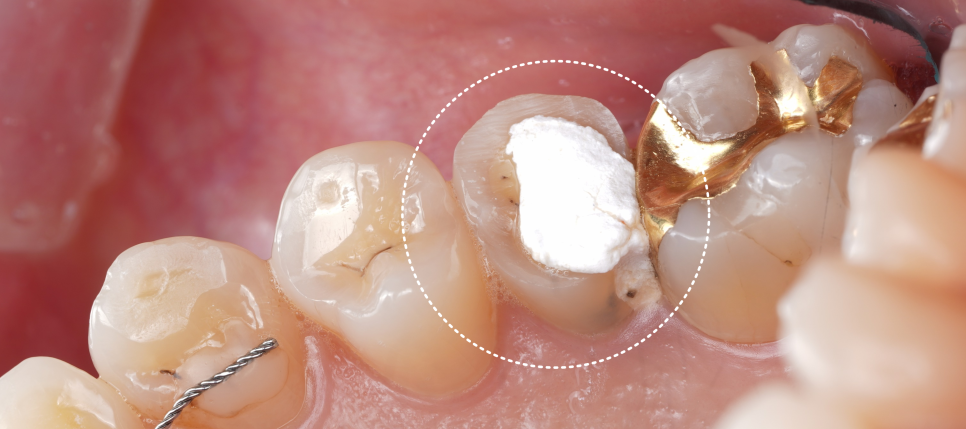

크라운 대신 ‘레진 빌드업’으로 결정했어요

저는 이렇게 설명드렸어요. “치아를 더 이상 깎지 않고 기존 충전물 제거 후 사라진 씹는 면과 벽을 레진으로 다시 만들어드리는 ‘레진 빌드업(오버레이에 가까운 형태)’으로 가는 게 좋겠습니다.”

촬영일 : 251124

기존에 남아 있던 충전물·임시재를 깨끗이 제거해서 충치와 재료 경계를 깔끔하게 정리했고 안쪽 바닥은 보험이 되는 재료(GI)로 두 면을 먼저 채워 뼈대(바탕)를 만들어 주기로 했죠.